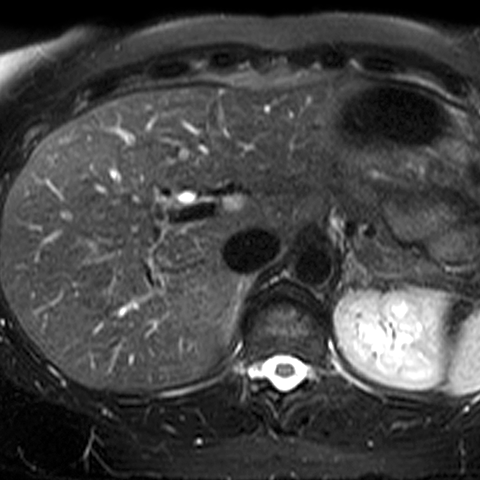

Normal Liver (T2- Weighted MR) [4 of 4]